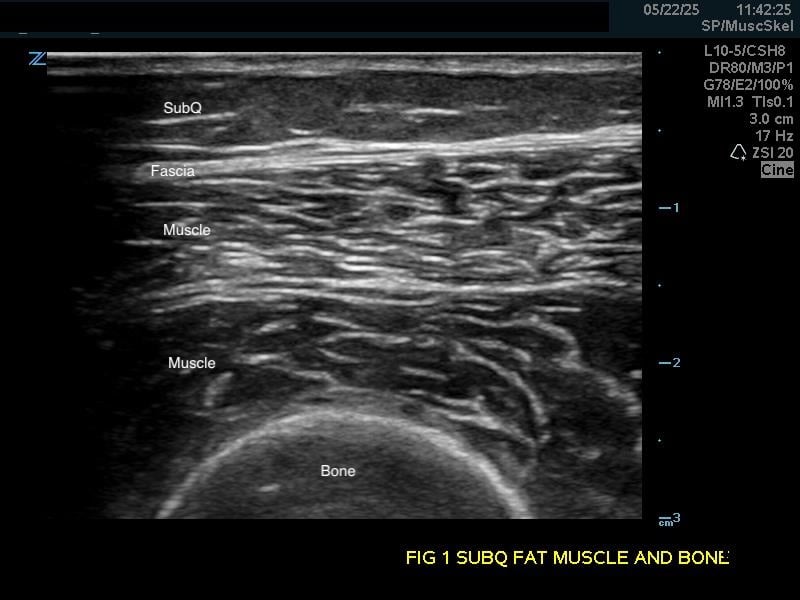

Figure 1a.

(A) Longitudinal view. Bone appears as a distinct bright echogenic line with no visible structures beneath, Subcutaneous fat appears relatively hypoechoic with thin septations of connective tissue.

Subcutaneous fat: Relatively hypoechoic with thin septations of connective tissue. The thickness of this layer varies and may require increasing the depth setting of your machine.

Muscle: Longitudinally, appears as slabs of striated hypoechoic tissue contained within the thin hyperechoic lines of fascia. Viewed transversely, muscle striations or septa appear dotted and punctate or form short lines. Fascial lines separate muscle compartments.